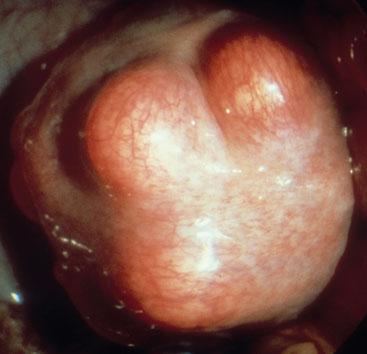

Fibroids

Fibroids are a benign growth of the uterine myometrium. They may grow in various places in the uterus: intra-mural - in the wall; subserosal - growing towards the pelvis; or sum-mucosal - growing into the uterine cavity. They may also grow from the cervix. They are more common in women of Africo-Caribbean extraction and more likely to be symptomatic in this group. For many, there may be no symptoms. However, they may cause menorrhagia (consider carrying out an FBC), undergo torsion causing pain, may be associated with infertility and may create pressure on the bladder affecting bladder emptying. During pregnancy, they may degenerate causing pain and fever.